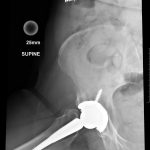

Pre-Op AP Pelvis

Harris Hip Score 60 (max=100) | Oxford Hip Score 25 (max=48)